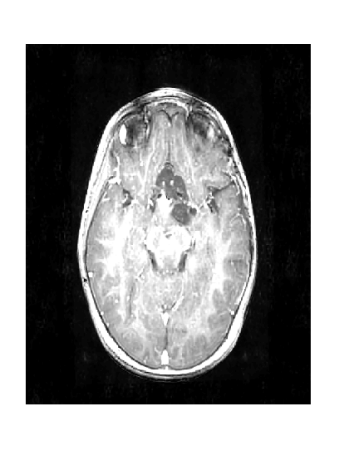

Figure 3 displays the reconstruction MSNR for the various test cases as cataloged in Table 1. Figures 1 and 2 display some examples of reconstructed images for cases of interest.

Due to its wide use in image processing, we consider the use of gradient sparsification with LACS-MRI. We show below that it is possible to produce image reconstructions with significantly higher Reconstruction SNR using gradient sparsification. We have repeated some of the simulations from above for different compression levels, , using the gradient transform to sparsify instead of the wavelet transform. We will refer to this as ”LACS-MRI with gradient sparsity.” We compared the performance of each sparsification method at each compression level using LACS-MRI and then compared this to the L1-W method. Again, we use a reference image and a follow-up image that we hope to recover as in Figure 8. We consider here only the phantom image, as it serves as a prime candidate for gradient sparsification, and is small enough that evaluation of all PDFs is computationally feasible.

Figure 12 shows the effect of a 2-fold scale difference on LACS-MRI image reconstructions. There are extensive streaking artifacts and significant detail is lost compared to the ground truth and the reconstruction using the modified method. Clearly, the Grayscale Compensation for Reference Based MRI Algorithm (GSC) can reduce these artifacts and help improve the visibility of structure.